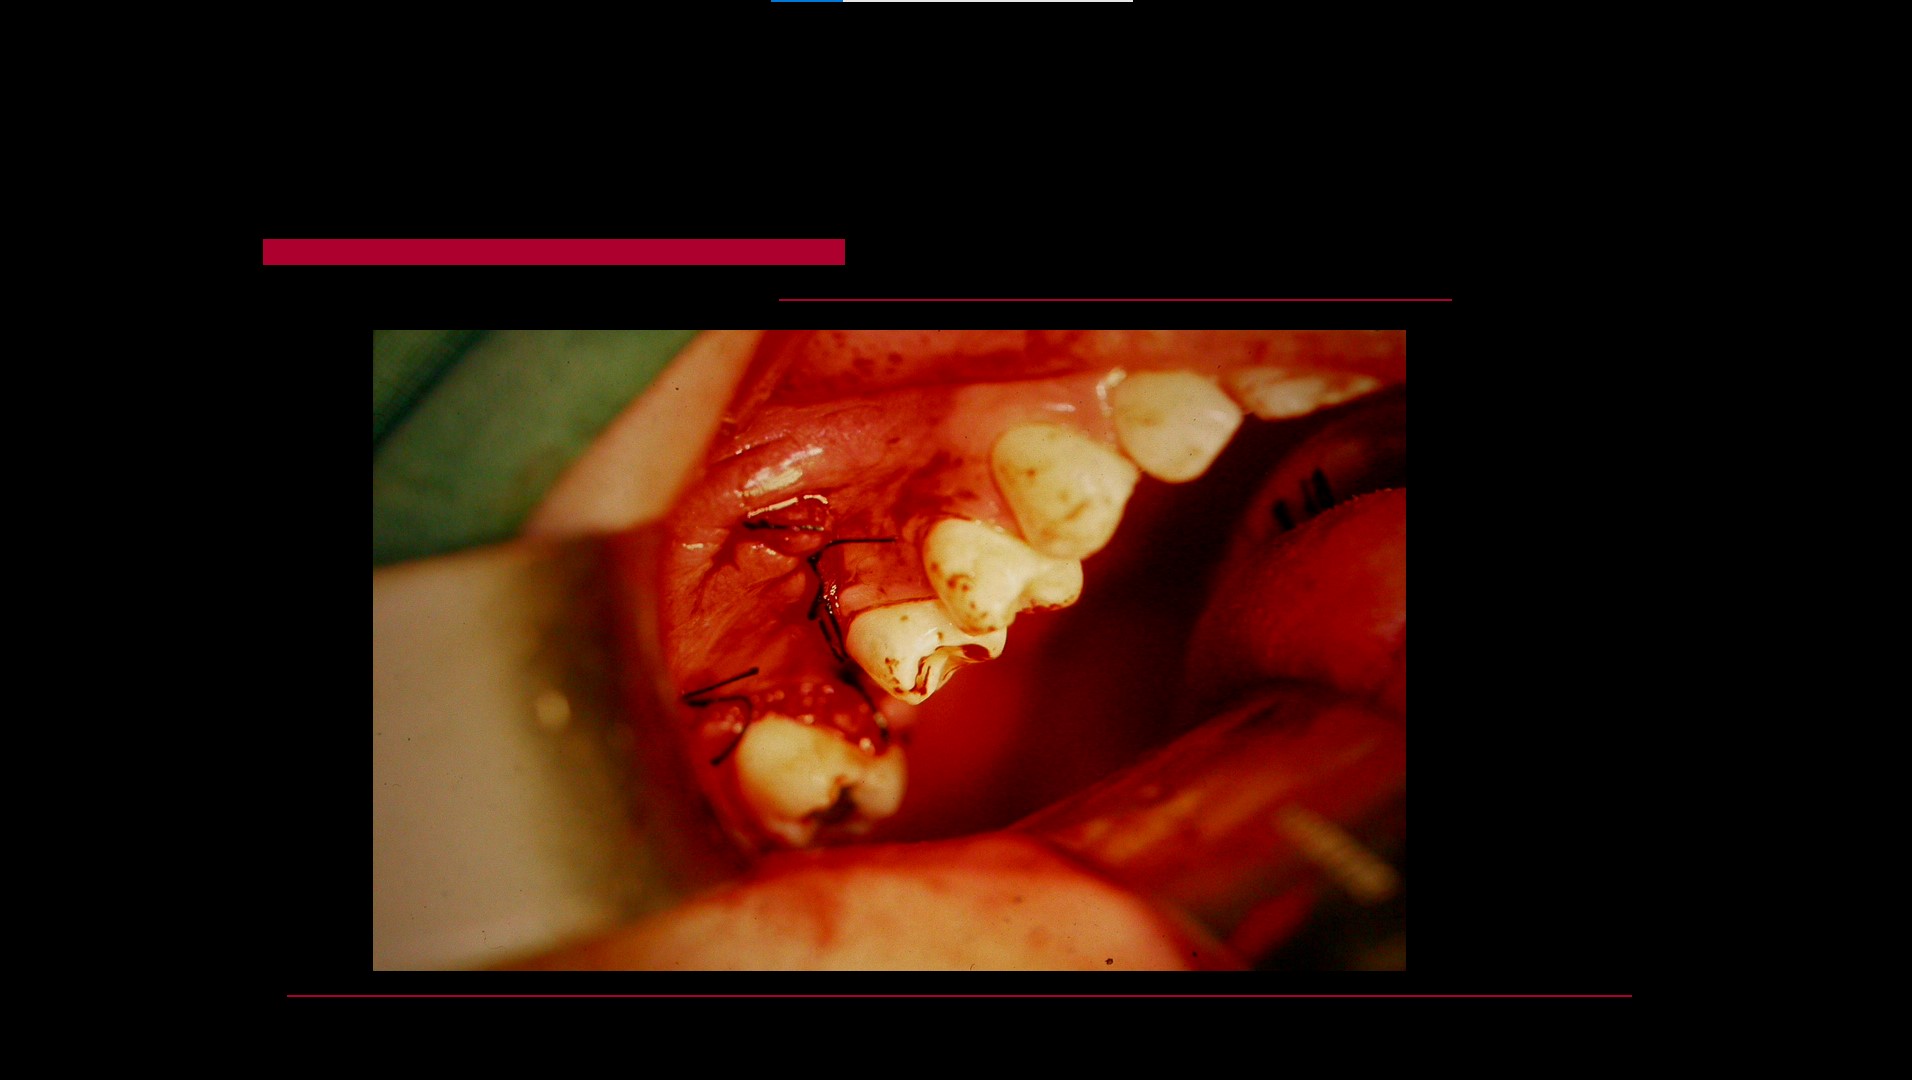

Impacted teeth